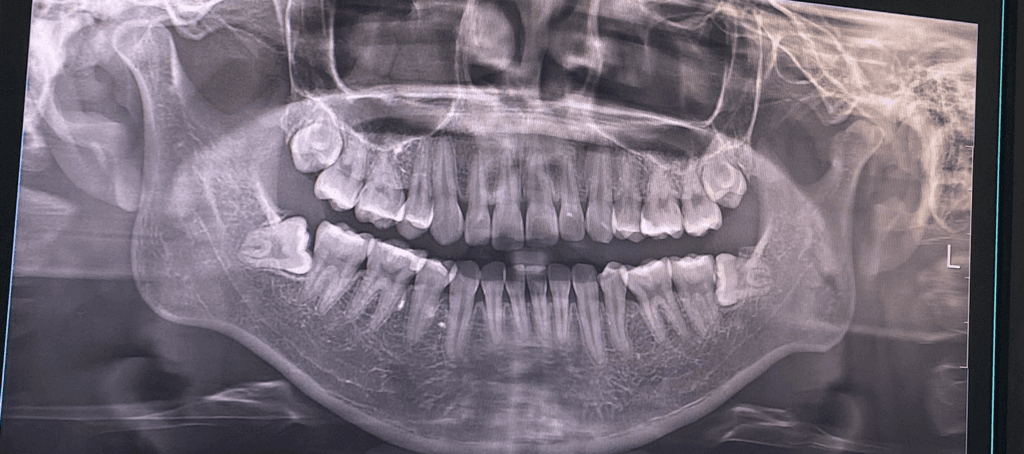

왼쪽 아래 사랑니는 수평 매복 사랑니로 치아를 부수고 뼈도 삭제해야 발치할 수 있을 것으로 보입니다.

왼쪽 위의 사랑니도 매복되어 뼈삭제 할 수도, 혹은 하지 않고 할 수도 있습니다.

저정도면 뼈삭제를 하더라도 많이하지는 않을꺼 같습니다 치아를 쪼개서 일단은 빼볼것같습니다.

잇몸 밖으로 보인다하더라도 잇몸을 열었을때 뼈가 사랑니를 덮고있으면 뼈삭제를 해야합니다